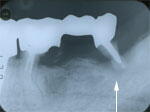

6.22年後

挺出した歯が虫歯になり、また周囲の骨も低下し、抜歯することにしました。(矢印の歯)

初診から22年半後でした。 |